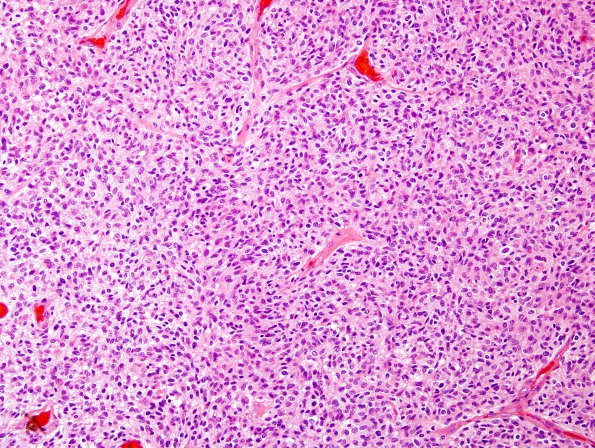

Washington University Experience | NEOPLASMS (GLIAL) | Glioblastoma, small cell type | 15A1 GBM, small cell (Case 15) H&E 5.jpg

Case 15 History ---- The patient was a 46 year old male who presented with seizures. MRI revealed an enhancing right frontal lesion. The lesion was initially biopsied and diagnosed as anaplastic oligodendroglioma at an outside hospital. Subsequent increase in size that year led to resection and similar pathologic diagnosis. ---- 15A1-3 Sections sent to BJH demonstrated an infiltrative glioma with a focally microcystic background containing an abundant chicken-wire type vasculature and focal calcification. Microvascular proliferation is seen, but there is no necrosis in the limited material provided. Mitoses are numerous and on one count, numbered 19/10HPF. Tumor cells bear negligible cytoplasm and a moderate degree of nuclear pleomorphism superimposed on a generally rounded to oval morphology. (H&E)